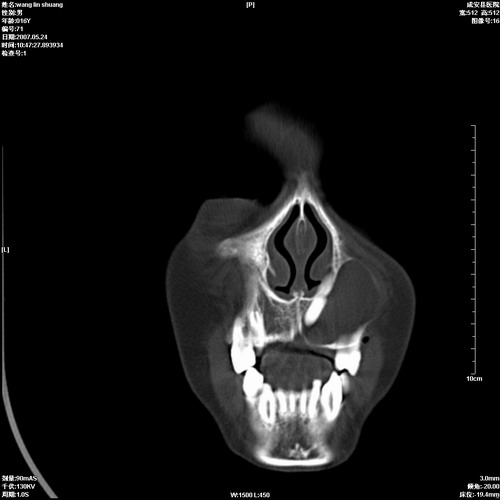

病人,男 16岁,鼻旁右肿胀,其余无不适感,ct图片

1、典型右侧根尖囊肿。

2、双侧上颌窦、筛窦、蝶窦炎

1\\左侧上颌骨含牙囊肿

2\\两上颌窦炎

右侧上颌骨含牙囊肿.双侧上颌窦炎症.

右侧上颌骨含牙囊肿.双侧上颌窦、蝶窦右侧炎症.

1、左侧上颌骨含牙囊肿。

本人同意根尖囊肿,双侧上颌窦、筛窦、蝶窦炎.

典型的右侧上颌骨含牙囊肿,双侧上颌窦、右侧蝶窦炎症。